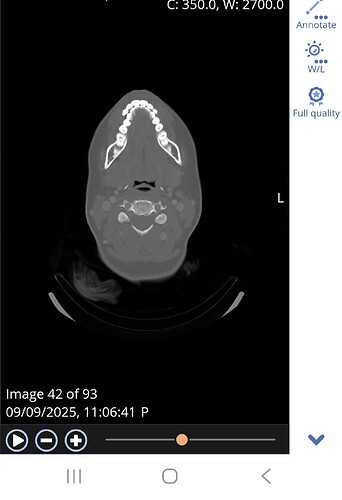

@Happyface12e not quite the right slice. Here’s an image of my C1 to help you know what to look for. Make sure you see the white circle in the top middle of the vertebrae:

Thanks for sharing. Is this what you mean?